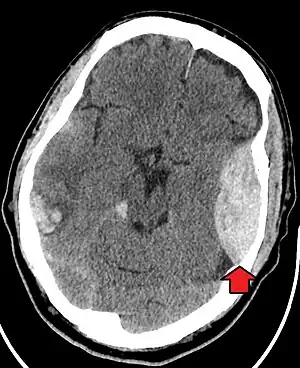

| Epidural hematoma as seen on a CT scan with overlying skull fracture. Note the biconvex shaped collection of blood. There is also bruising with bleeding on the opposite side of the brain. | |

Epidural hematomas usually appear convex in shape because their expansion stops at the skull's sutures, where the dura mater is tightly attached to the skull. Thus, they expand inward toward the brain rather than along the inside of the skull, as occurs in subdural hematomas. Most people also have a skull fracture.[3]

Non-contrast CT scan of a traumatic acute hematoma in the left fronto-temporal area. -